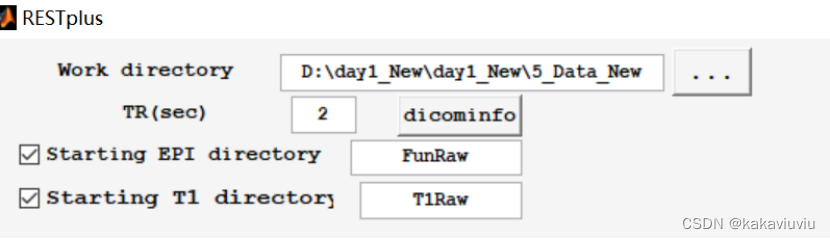

剩下几步用restplus做(实际上上述步骤都可以用restplus批量处理)

Restplus

Set path--add with subfolders-添加restplus的文件夹

打开pipeline

Matlab切路径到restplus

work directory选择所用文件的上一级文件夹

EPI directory选择功能像,T1 directory选择T1的文件夹(原始数据)